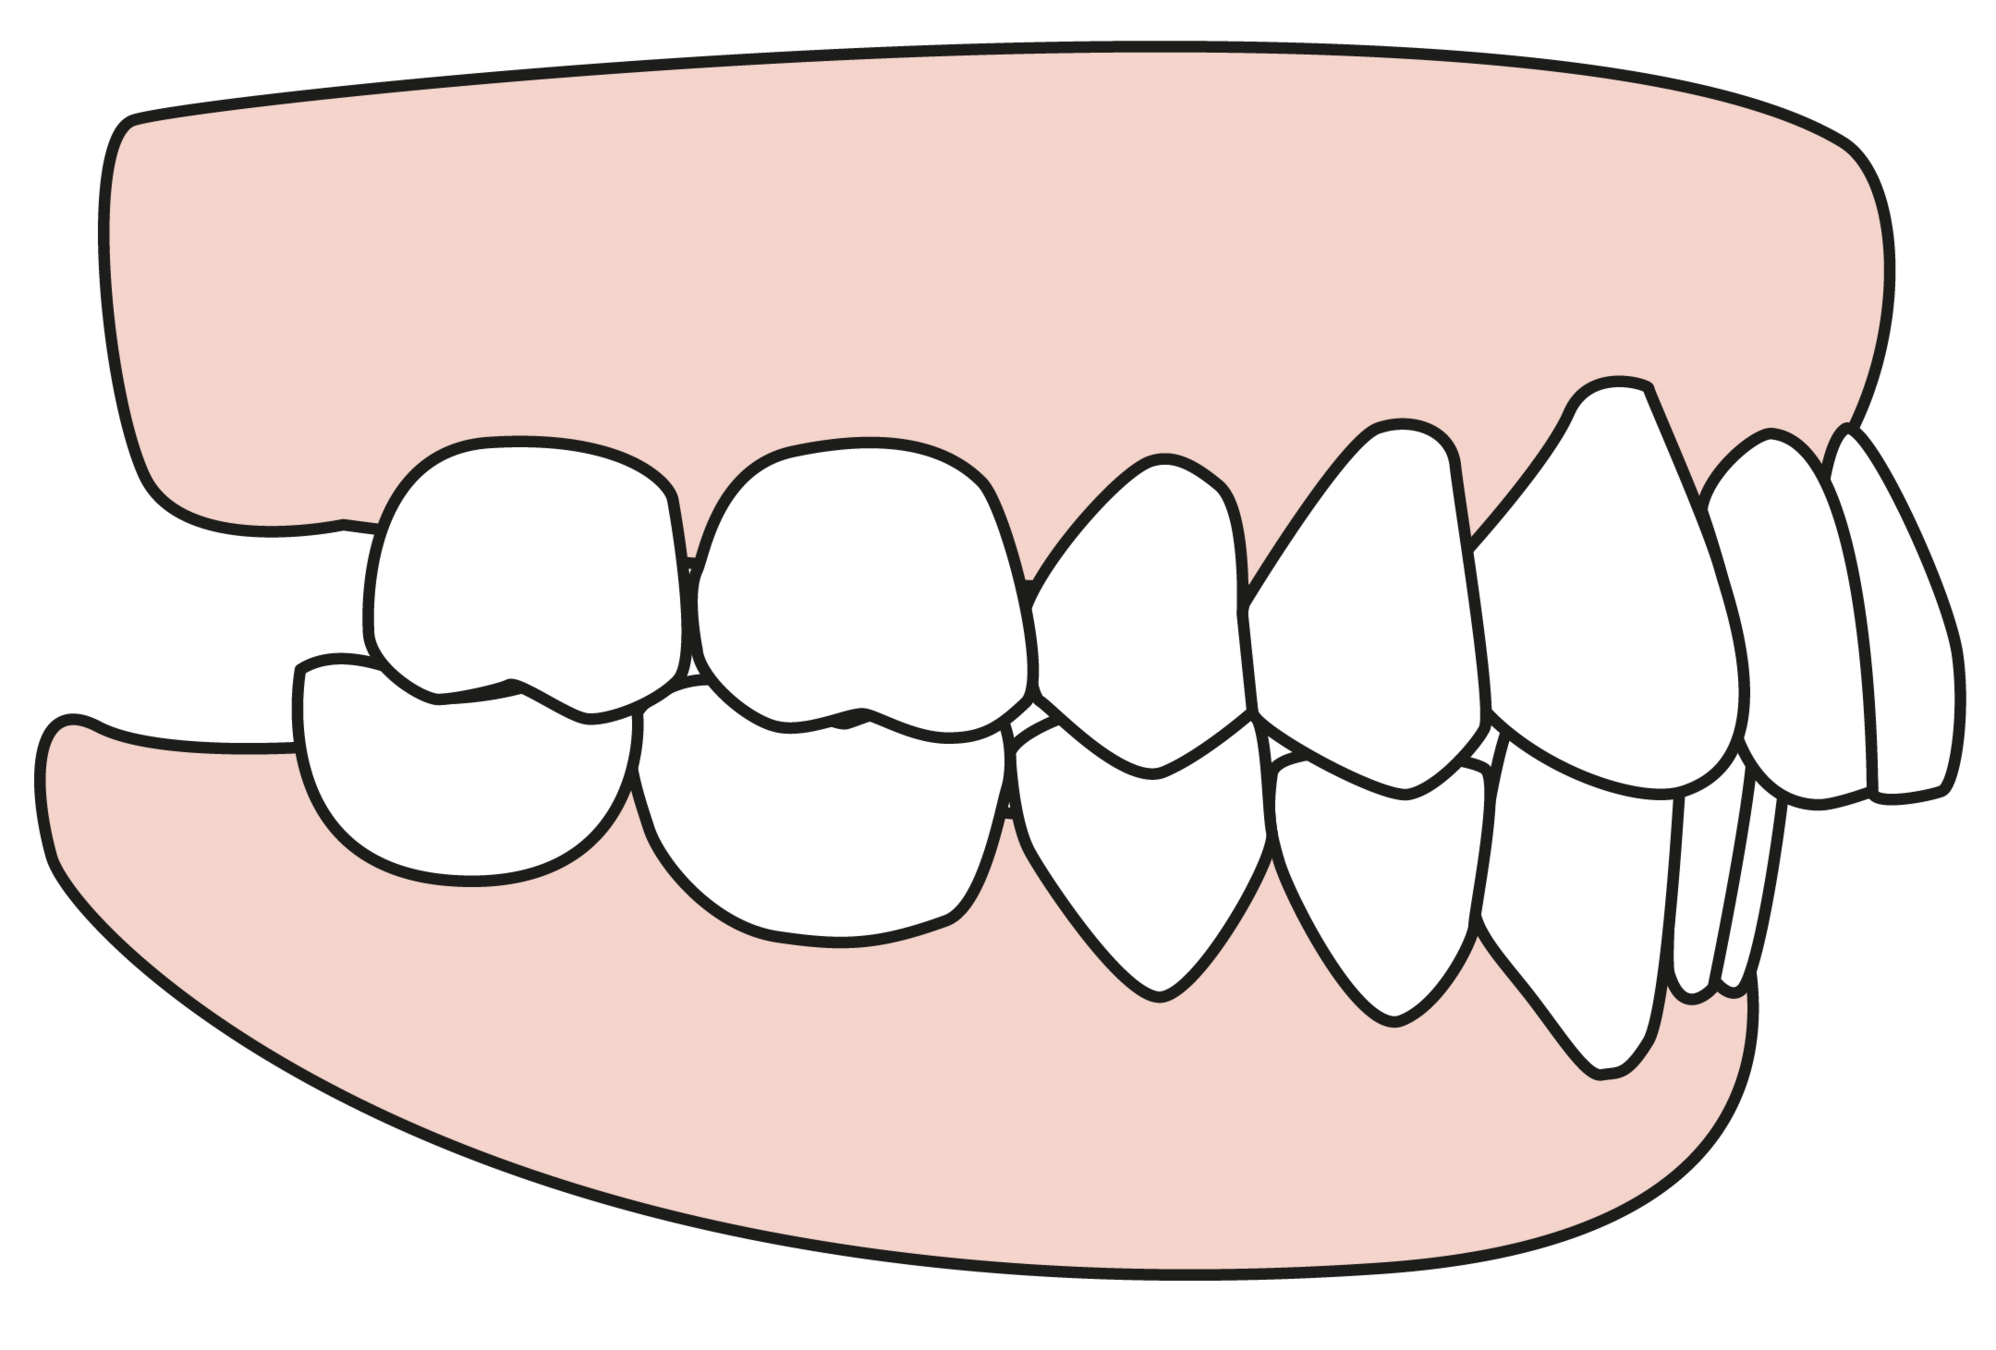

DO YOU HAVE DENTURES?

Do you have cosmetic or restorative work done?

How many teeth are you missing?

Do you an overbite or underbite?

Do you have tooth decay?

Do you have periodontal disease?

Do you have bruxism?

Do you have TMJ?

Do you have allergies to acrylic or stainless steel?

Taking Impressions

Taking Impressions

Taking Impressions

Taking Impressions

Taking Impressions

Taking Impressions

Taking Impressions

Taking Impressions

Taking Impressions

Taking Impressions

Taking Impressions

Taking Impressions

Taking Impressions

Taking Impressions

Taking Impressions

Taking Impressions

Taking Impressions

Taking Impressions

Taking Impressions

Taking Impressions

Taking Impressions